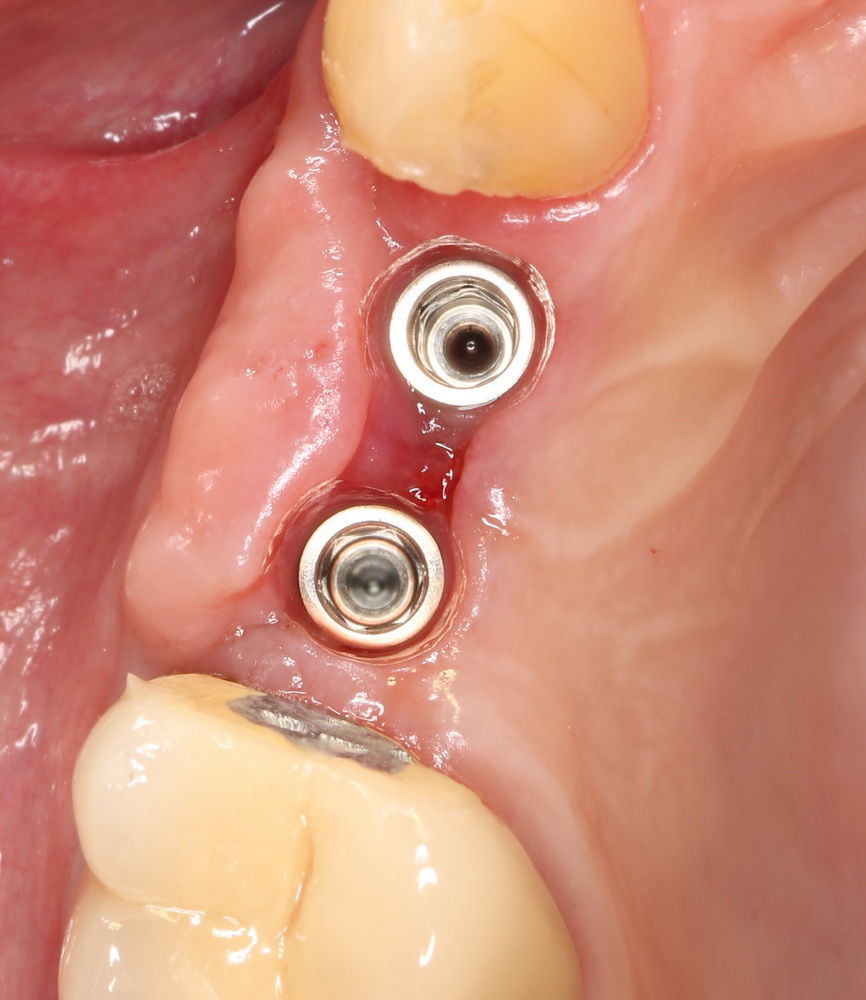

Мы ставим формирователи десны:

параллельно восстанавливая достаточный слой прикрепленной десны. Через неделю: